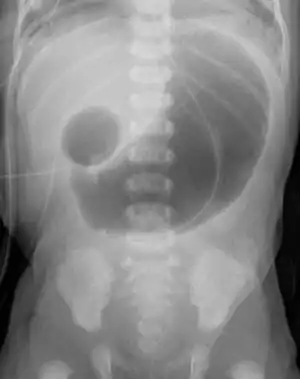

Double bubble (radiology)

In radiology, the double bubble sign is a feature of pediatric imaging seen on radiographs or prenatal ultrasound in which two air filled bubbles are seen in the abdomen, representing two discontiguous loops of bowel in a proximal, or 'high,' small bowel obstruction. The finding is typically pathologic, and implies either duodenal atresia, duodenal web, annular pancreas, and on occasion midgut volvulus, a distinction that requires close clinical correlation and, in most cases, surgical intervention.[1][2][3]